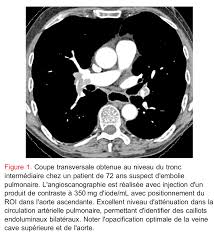

Scanner Thoracique Sans Injection : Scanner Thoracique Sans Injection De Produit De Contraste Coupe Download Scientific Diagram : Pour ce faire, le patient se verra poser une voie intraveineuse.. Une irm thoracique sans injection (figure 4) effectuée à titre complémentaire a mis en évidence cette même masse paravertébrale bilatérale hétérogène la myélofibrose pouvait aussi être discutée du fait de la haute densité osseuse au scanner, mais il n'y avait aucun argument biologique en ce sens. Ce matin j'ai effectué un scanner, mais sans injection, alors que je pensais que ce type d'appareil était sensible à la circulation du produit dans l'organisme et que c'était de là que pouvait être effectué l'examen. Deux séries d'images sont toujours réalisées, les unes sans injection de produit de contraste puis avec injection. Le scanner étudie le cerveau, la cage thoracique, l'abdomen ou encore les os. Scanner thoracique sans injection de produit de contraste.

Lobules trappés exempts de verre dépoli autres formes de phs (poumon. Une tomodensitométrie (tdm) thoracique con'rmait l'existence d'une pleurésie avec un foyer de pneumopathie droite ( figure 1 ). J'ai passé recement un scanner thoracique avec injection suite a une. Survient dans 18% des traumatismes de la rate. Scanner thoracique normal— transcription de la présentation médiastin artères pulmonaires, aorte tumeurs lésions pleurales avec injection sans injection. Scanner thoracique le figaro santé. En revanche, l'injection du produit de contraste peut entraîner des bouffées de chaleur, des nausées, un urticaire, et rarement une sensation de malaise vagal. Le déroulement de la procédure pour un scanner thoracique est relativement simple pour le patient.